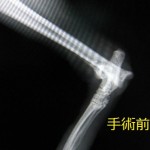

足根関節というのはいわゆるあしくびの部分の関節で、交通事故などの外力により脱臼を引き起こします。

骨折・脱臼の整復には、プレート、スクリュー、ピンを用いた内固定が一般的ですが、